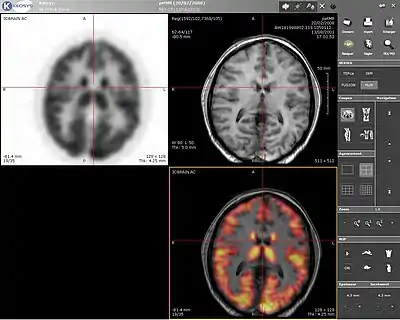

پت-ام آر ای (PET-MRI) نام یک سیستم مولتی مدالیته است که از ترکیب ام آر آی و پت اسکن به وجود میآید.

ایدهٔ ترکیب PET/MRI در سال ۱۹۹۰ قبل از این که PET/CT به صورت تجاری در دسترس قرار گیرد به وجود آمد و در سال 2011 در ماه ژوئن توسط FDA تأیید شد. برخلاف PET/CT که دو جزء تشکیل دهنده پشت سر هم قرار میگیرند و از طریق تخت بیمار به هم مرتبط میشوند در PET/MRI، اسکنر PET درون دستگاه MRI قرار گرفته و امکان تصویربرداری همزمان فراهم شدهاست.[1]

MRI نه تنها اطلاعات آناتومیکی با رزولوشن فضایی بالا فراهم میکند و کنتراست بافت نرم آن نسبت به CT بسیار بیشتر است امکان استفاده از FMRI و MRS را نیز فراهم میکند. مزیت دیگر MRI بر CT عدم حضور تشعشعات یونیزهکننده است. معمولاً نیازی به تزریق عاملهای کنتراست زا که ممکن است تأثیرات جانبی بر بیمار داشته باشد، نیست. تصویربرداری همزمان PET وMRI زمان تصویربرداری را کاهش میدهد همچنین آرتیفکتهای حرکتی بین دو تصویر کاهش مییابند. مشکلات PET/MRI را میتوان در هزینه بالا سرعت کم و دشواری در تصحیح تضعیف تصاویر PET دانست.